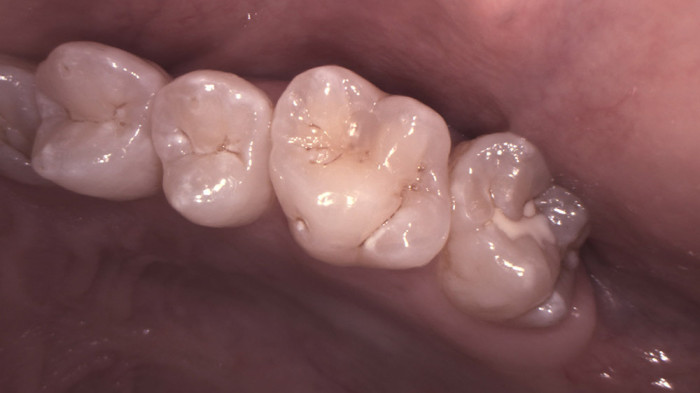

Makro-Aufnahmen

Zur Vergrößerung feinster Zahn- und Zahnfleischstrukturen, empfohlen zur Erkennung kleinster Läsionen, fehlerhafter Übergänge von Füllungsmaterial oder Kronen zum Zahn sowie zur ersten Untersuchung von Wurzelkanälen.